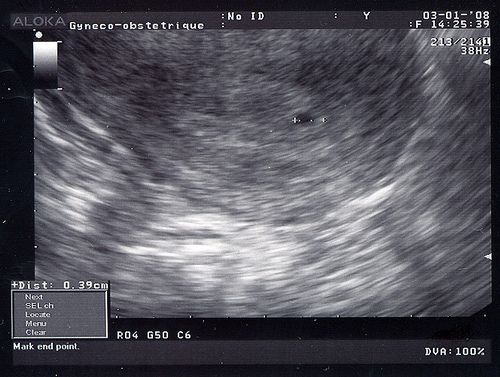

"sa", ça veut dire "semaines aménorrhées", des semaines sans règles. Il y en a 42 à faire. Elles se calculent depuis le premier jour de mes dernières règles. C'était le 28 novembre. Sur cette échographie, je suis à tout juste 5 sa.

"sg", ça signifie "semaines de grossesse", c'est ton âge réel depuis le jour où tu as été conçu par papa et moi. Il y a toujours deux semaines de décalage entre le début des règles (donc le 28 novembre) et la période où c'est possible de concevoir un enfant (pour toi, le 12 décembre). Donc sur cette photo, tu as tout juste 3 semaines.

On voit juste le petit sac dans lequel tu es en train de grandir. Le sac mesure à peine 4 mm et toi tu fais 0,1 mm! C'est vraiment minuscule!